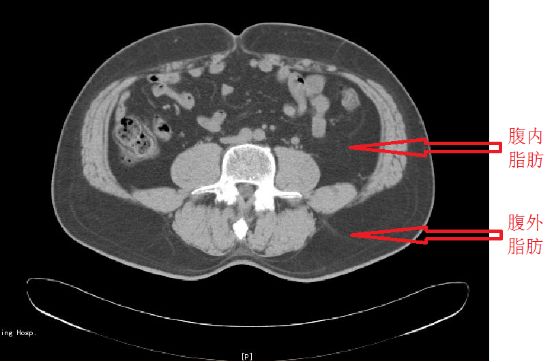

CT 或 MRI 技术:被认为是测量内脏脂肪的先进手段,是目前公认的测量内脏脂肪含量的金标准。

腹部脂肪的 CT 测量,要求病人在空腹状态下采用 CT 行腹部扫描(如下图)。当然,这种测试一般是用于科研,很少有人为了准确测量内脏脂肪跑去医院做CT 或 MRI检查吧。